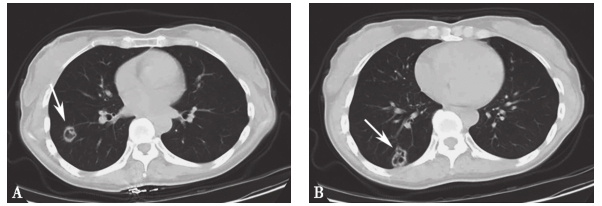

年1月患者无明显诱因出现咯血,为痰中带血,无低热、盗汗、消瘦等不适,肺部CT提示“右肺下叶有两个不规则空洞,壁厚薄欠均匀,边缘较毛糙,内壁尚光滑,空腔不规则并见分房,局部胸膜轻度牵拉增厚”(图1),血及肺泡灌洗液的曲霉半乳甘露聚糖(GM)检测均阳性,痰真菌培养、细菌培养及痰找抗酸杆菌均阴性,肺泡灌洗液细胞分类正常,结核菌素纯蛋白衍生物(PPD)试验阴性,肿瘤标志物不高,考虑患者为“肺类风湿结节坏死、肺烟曲霉感染、肿瘤不除外”,建议行肺穿刺活检明确病变性质,但患者拒绝。

图1 2010年1月胸部CT

A、B中箭头示右肺下叶不规则空洞

予患者口服伊曲康唑200mg/d,抗真菌感染治疗2个月后,复查胸部CT空洞无好转,遂行右下肺叶切除术,病理提示“肺内多发结节,部分结节中心坏死,炎性渗出,周围纤维结缔组织增生包裹,淋巴细胞浸润,可见个别巨细胞。另有部分结节纤维化,炎症细胞浸润。病变内及周围血管疑有血管炎病变。支气管断端未见明显异常,支气管周边淋巴结反应性增生”。特殊染色结果:弹力纤维染色(+),抗酸染色(−)。考虑为“类风湿结节可能”。此后咯血好转。